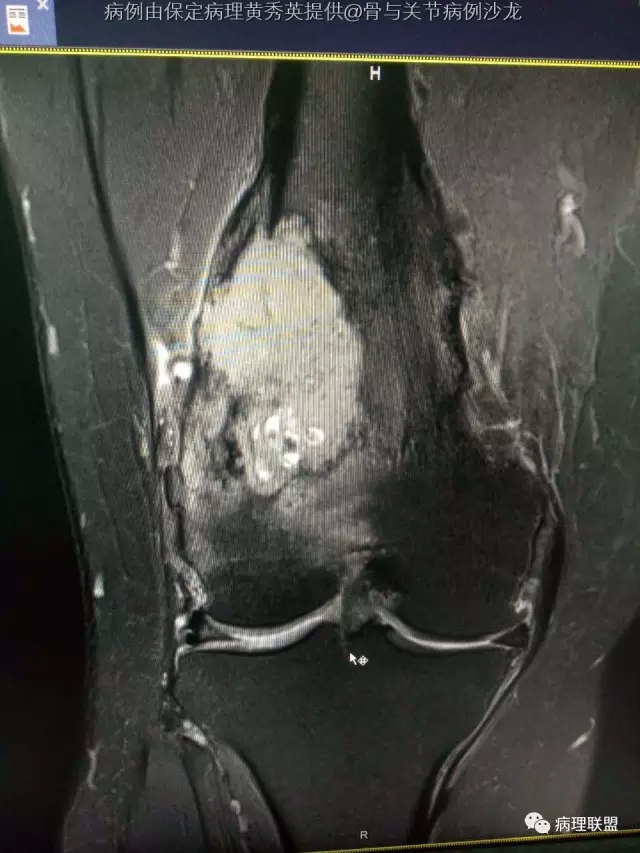

女67岁,股骨下端肿物约6cm,(病例由保定病理黄秀英提供,致谢!)